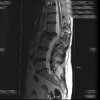

Tumores vertebrales y hernia lumbar

Espondilolistesis